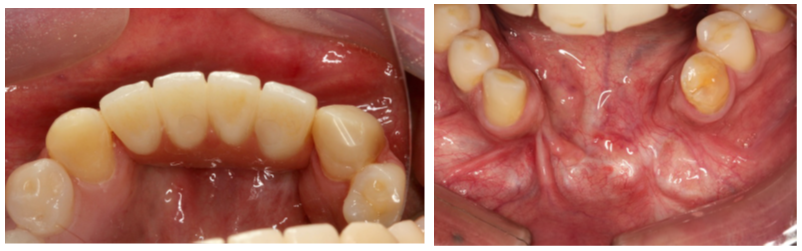

Na sequência de imagens, podemos perceber a formação de gengiva inserida e a devolução do vestíbulo que tinha sido totalmente perdido.

Tecnologia avançada, produtos de excelência, planejamento correto e prótese com ótima estética e função devolveram qualidade de vida e melhoraram a autoestima ao paciente.